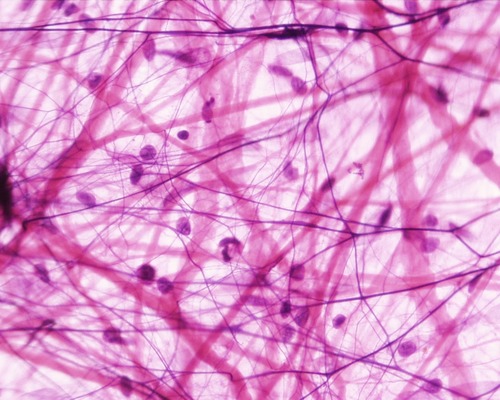

areolar connective tissue

bind skin to underlying organs, fill spaces between muscles, and nourish epithelium

fibroblast

Large star shaped cells that secrete proteins into ECM